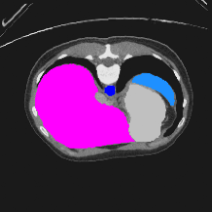

Transformers have made remarkable progress towards modeling long-range dependencies within the medical image analysis domain. However, current transformer-based models suffer from several disadvantages: (1) existing methods fail to capture the important features of the images due to the naive tokenization scheme; (2) the models suffer from information loss because they only consider single-scale feature representations; and (3) the segmentation label maps generated by the models are not accurate enough without considering rich semantic contexts and anatomical textures. In this work, we present CASTformer, a novel type of generative adversarial transformers, for 2D medical image segmentation. First, we take advantage of the pyramid structure to construct multi-scale representations and handle multi-scale variations. We then design a novel class-aware transformer module to better learn the discriminative regions of objects with semantic structures. Lastly, we utilize an adversarial training strategy that boosts segmentation accuracy and correspondingly allows a transformer-based discriminator to capture high-level semantically correlated contents and low-level anatomical features. Our experiments demonstrate that CASTformer dramatically outperforms previous state-of-the-art transformer-based approaches on three benchmarks, obtaining 2.54%-5.88% absolute improvements in Dice over previous models. Further qualitative experiments provide a more detailed picture of the model's inner workings, shed light on the challenges in improved transparency, and demonstrate that transfer learning can greatly improve performance and reduce the size of medical image datasets in training, making CASTformer a strong starting point for downstream medical image analysis tasks.